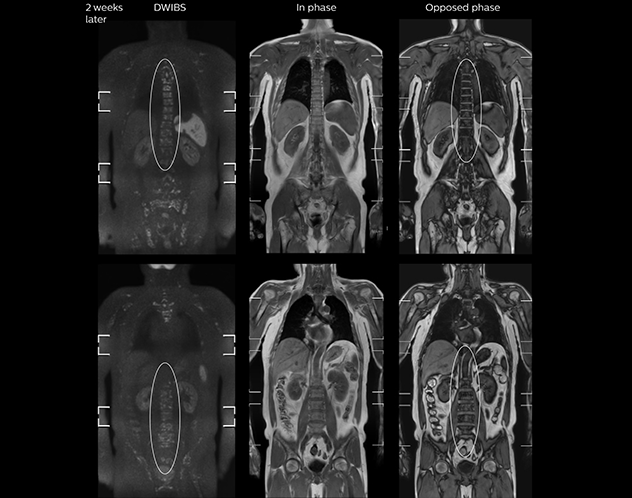

“When we limited the scan coverage to the area from neck to femur, we could fit more clinical information in approximately the same scan time. So, we added coronal mDIXON, sagittal T1-weighted, and sagittal STIR sequences to our examination, instead of performing only axial DWIBS and coronal single-shot TSE scans.”

The single shot T2-weighted TSE images are used for morphology and compared to DWIBS images to identify T2 shine-through. Sagittal STIR images are used in patients with inflammation or bone metastasis.

mDIXON FFE enriches the whole body exam without scan time penalty

Kawasaki Sawai Hospital’s whole body protocol also includes an mDIXON FFE sequence. Because mDIXON provides images for four contrast types – water only, fat only, in-phase and out-of-phase – from a single acquisition, it is useful in many ways.

“mDIXON FFE allows us to quickly get information we need to assess the presence of fat. That gives us more information when we need to diagnose bone lesions, and when we are asked to judge fat-containing lesions such as hepatocellular or renal carcinoma,” Dr. Nobusawa says.

“The mDIXON fat images can help us to differentiate fatty bone marrow from bone lesions. This is especially useful in elderly people, who tend to have fattier bone marrow. The water images provide a high signal-to-noise ratio in the intestinal canal, which is valuable for visualizing lesions in the colon,” he says.

“In-phase and out-phase sagittal T1-weighted FFE images help us to visualize and further characterize bone lesions such as metastasis and bone-marrow hyperplasia that have high signal on DWI. These images are also used throughout radiotherapy, to monitor changes in the fatty bone marrow.”